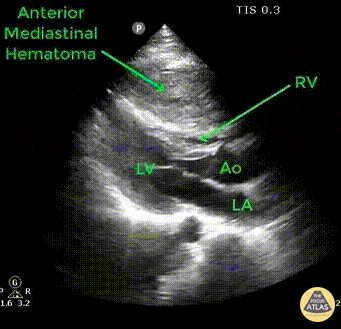

Pt presents to ED following an unrestrained head-on MVC with blunt force trauma to chest. Compressing the RV is an anterior mediastinal hematoma seen in this parasternal long axis view secondary to a sternal fracture. Image courtesy of Robert Jones DO, FACEP @RJonesSonoEM Director, Emergency Ultrasound; MetroHealth Medical Center; Professor, Case Western Reserve Medical School, Cleveland, OH View his original post here